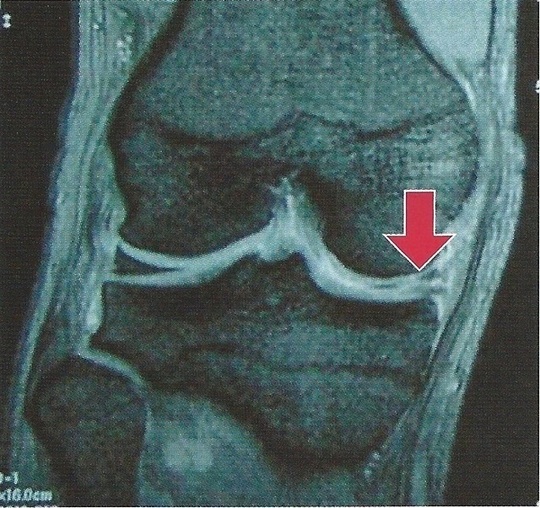

内側半月の変性断裂